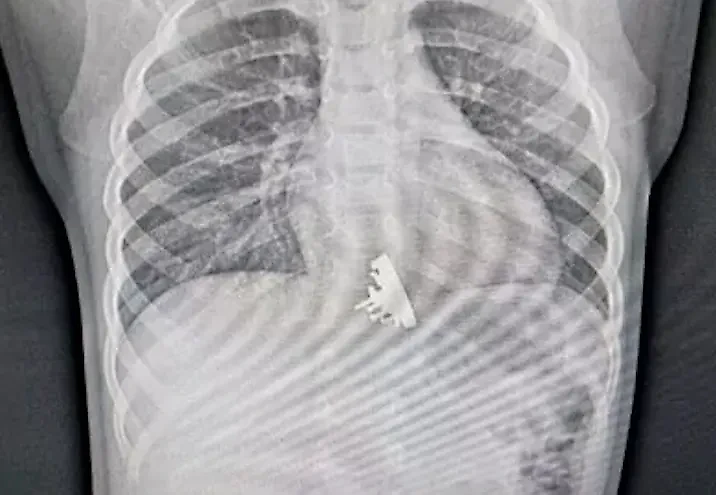

В Иркутске в Ивано-Матренинскую детскую клиническую больницу попала двухлетняя девочка. Осмотрев её рентгеновские снимки, врачи были шокированы. В пищеводе ребёнка застрял металлический игрушечный крейсер "Аврора". Оказалось, что малышка проглотила часть конструктора во время игры.

"Мы сразу заметили, что эта вещь имеет довольно острые выступающие части. Они цеплялись за стены пищевода девочки и царапали его", — рассказал врач отделения эндоскопии ДКБ Илья Пикало в беседе с kp.ru.

Изъять игрушку оказалось сложнее, чем обычные находки в виде монет и прочих гладких предметов, однако специалисты справились и после "абордажа" оставили девочку под наблюдением медперсонала.